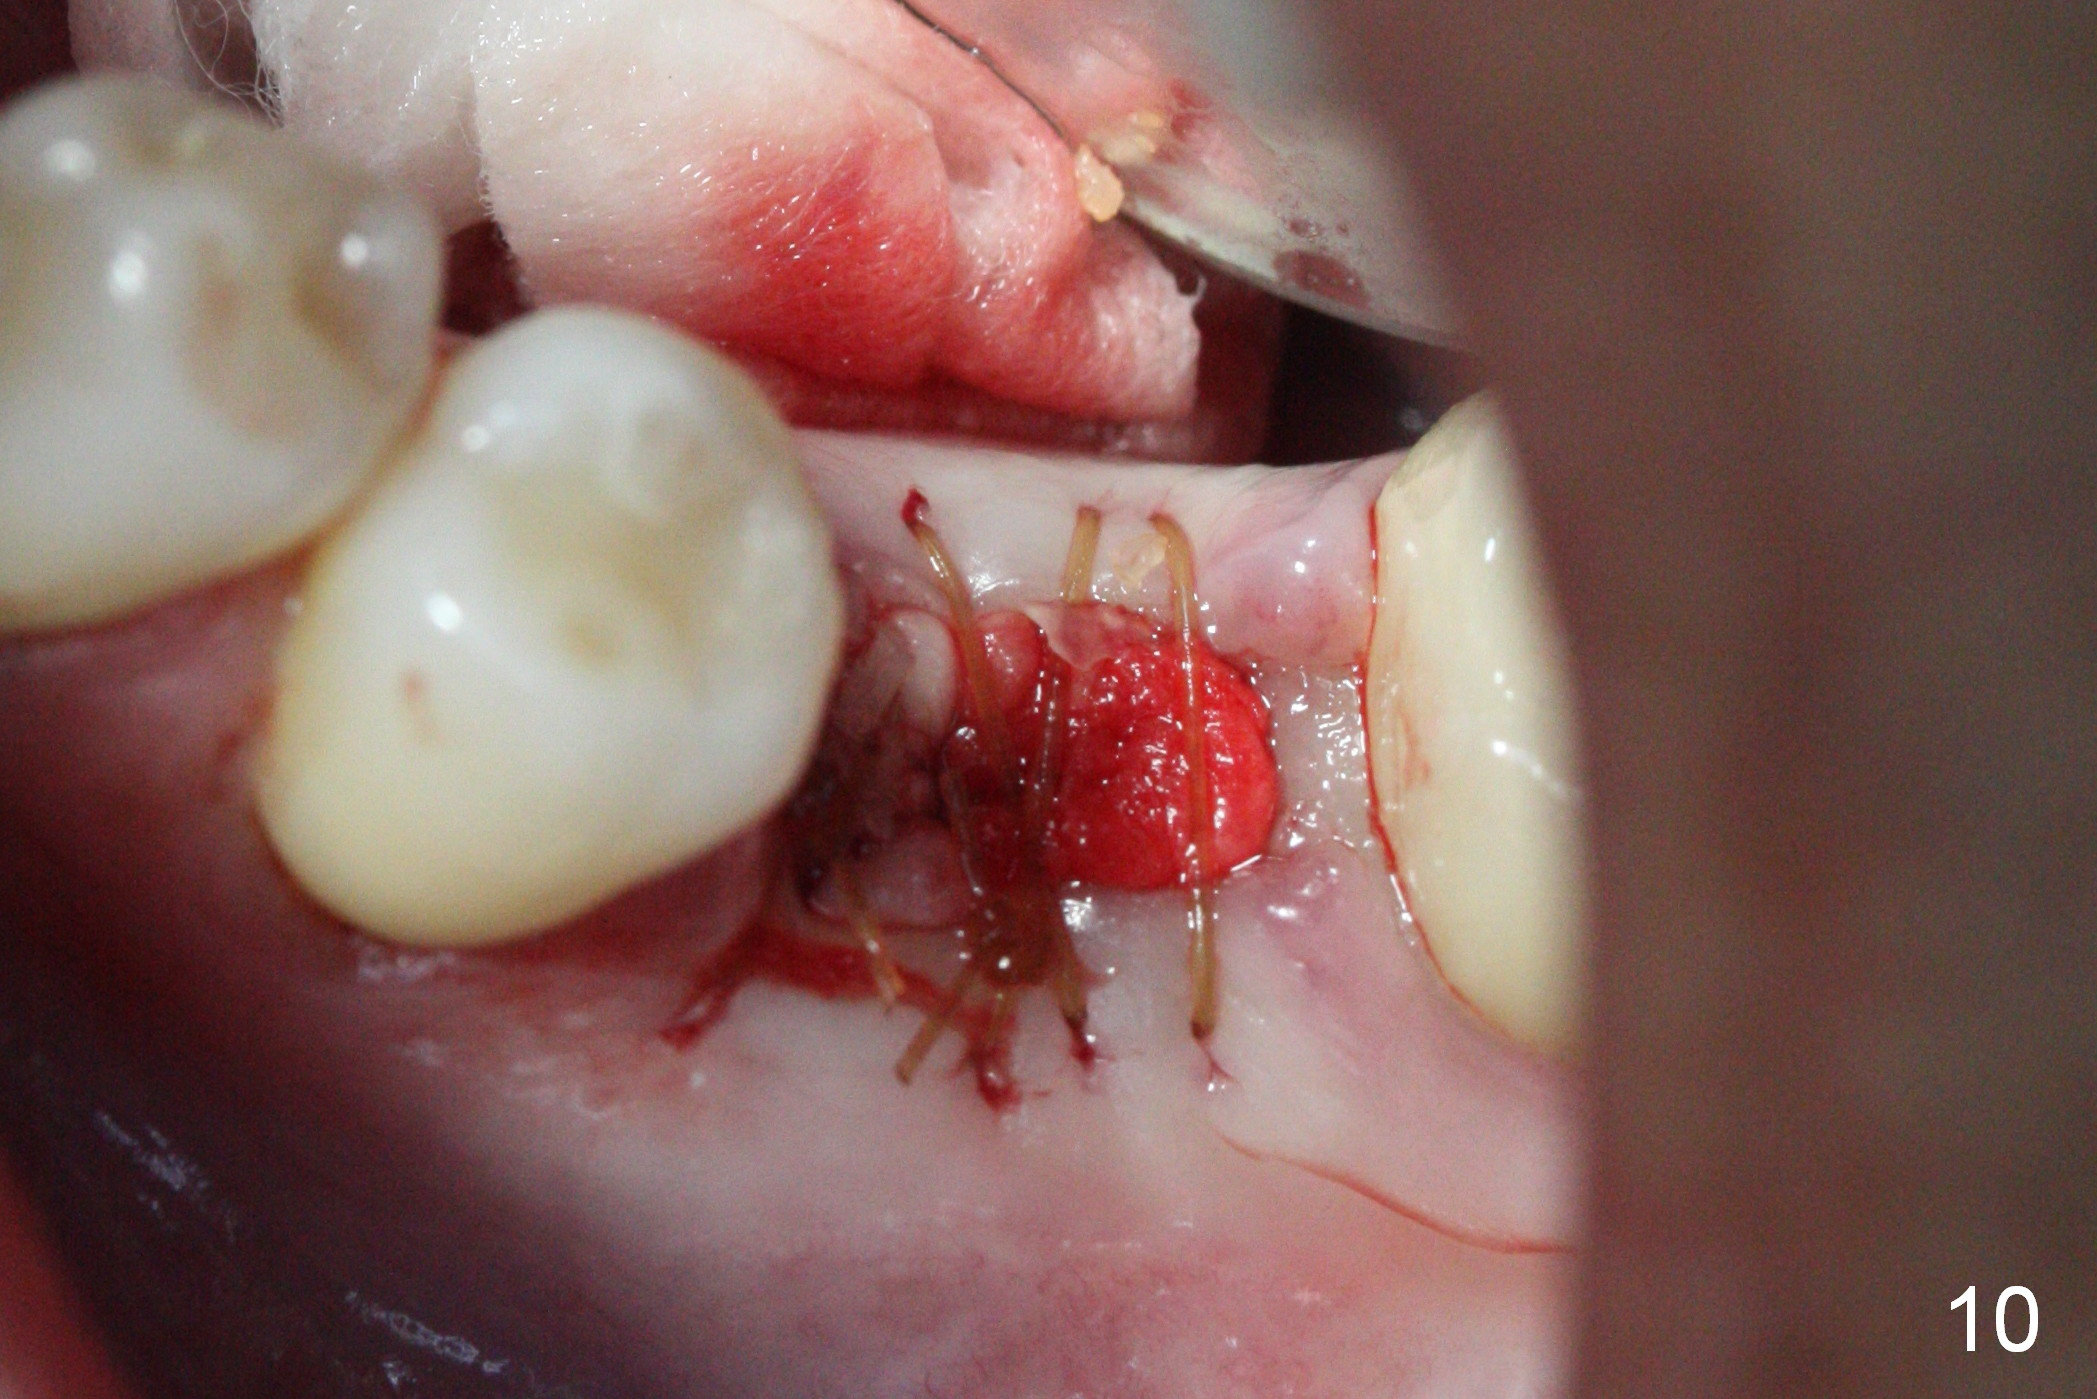

The tooth #19 is easy to get loose, but it cannot be luxated. After sectioning and extraction (Clindamycin), the septum is found to be thin (Fig.4). A surgical fissure bur is used to initiate osteotomy, followed by 1.6 mm pilot drill. It is difficult to use Marking bur (wobbling over the basically pointed septum). It is impossible to use 4.3 mm Magic Drill (MD, one drill system), since it jumps. The smallest MD has to be used (2.8 mm). When the next drill (3.3 mm) is being used for 13 mm with stopper (Fig.5), the patient experiences transient pain. The depth is suggested from the design in Fig.2. The thin septum appears not to be a reliable landmark. When block anesthesia is administered, the initial depth should be shortened. The drill appears to be close to the Inferior Alveolar Canal (Fig.5). Then the depth changes to 11 mm with the following drills (3.8 and 4.3). The mesial and distal walls of the septum are gradually perforated. A 5x9 mm dummy implant is placed only after using 4.8 mm drill (Fig.6). The implant appears to be short. When a longer implant is placed (5x11 mm), it does not easily enter the osteotomy, either sliding into the mesial or distal socket with the implant separating from the implant driver. It appears that a premount implant is appropriate in this situation. When the 5x11 mm implant is finally seated with stability, it is 6 mm apical to the gingival margin. The longest cuff of IBS abutment is 4 mm. A longer implant is needed (Fig.7, 5x13 mm). Placement is not easy as mentioned above. Insertion torque is <20 Ncm when the patient experience a little discomfort. A 6.5x4(4) mm pair abutment is placed (A), apparently proper for restoration. Allograft is placed (Fig.8 *) prior to immediate provisional. The patient complains of bad smell from the site 24 days postop. When the provisional is removed, the abutment is found to be mobile. When the latter is removed with local anesthesia, bone graft granules are attached to the socket above the lightly mobile implant (Fig.9). In fact the latter appears to be stable after a few turns by finger. A healing screw is placed; the socket is closed with collagen plug and 4-0 Chromic gut sutures (Fig.10). It appears that a larger implant should have been used to achieve higher torque. Two months later (3 months postop), the coronal end of the implant is partially exposed. A 5x4 mm healing abutment is placed. It appears that the implant is stable. The implant appears to have osteointegrated 4 months postop (Fig.11). Impression is taken.